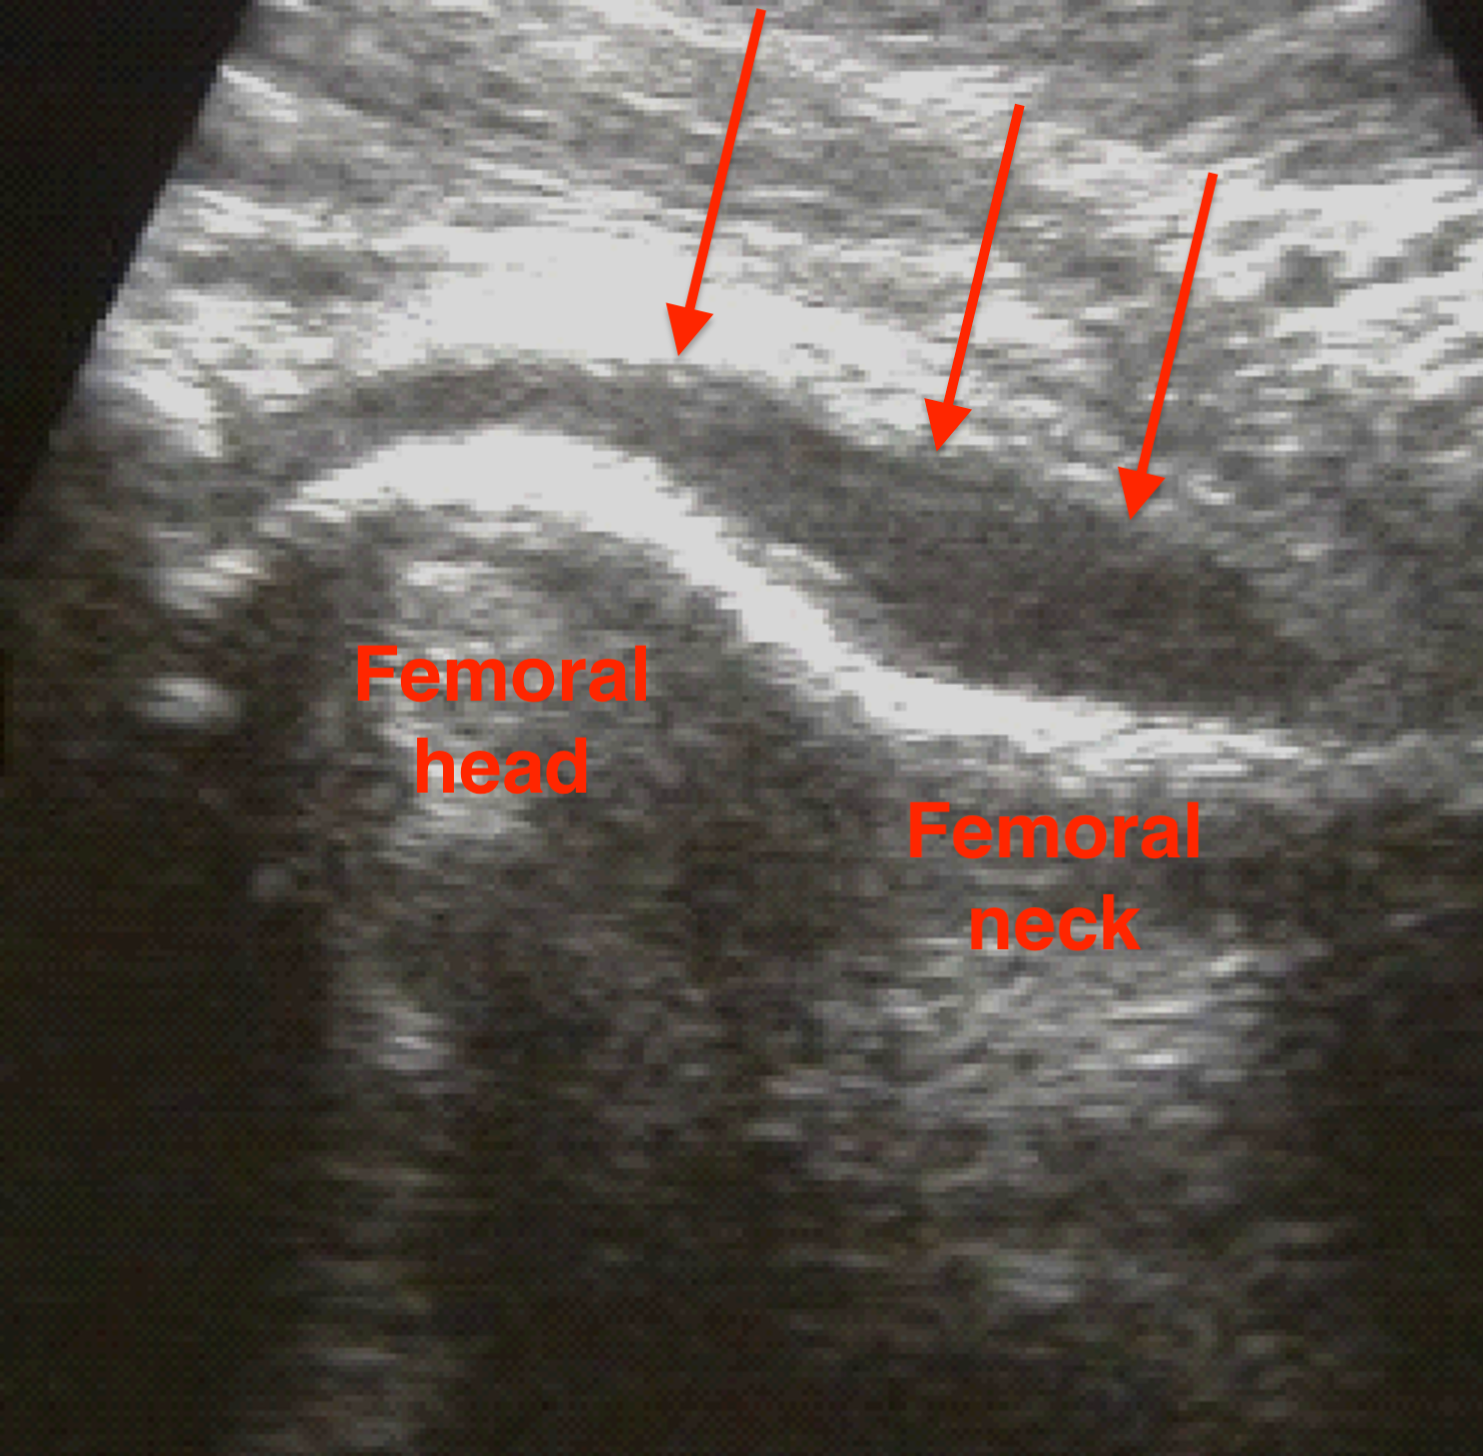

Ultrasound

Effusion

Hip ultrasoundHip ultrasound

Joint aspiration

Findings

- WBC >50,000 cells / uL

> 50% polymorphonuclear leukocytes (PMNs)